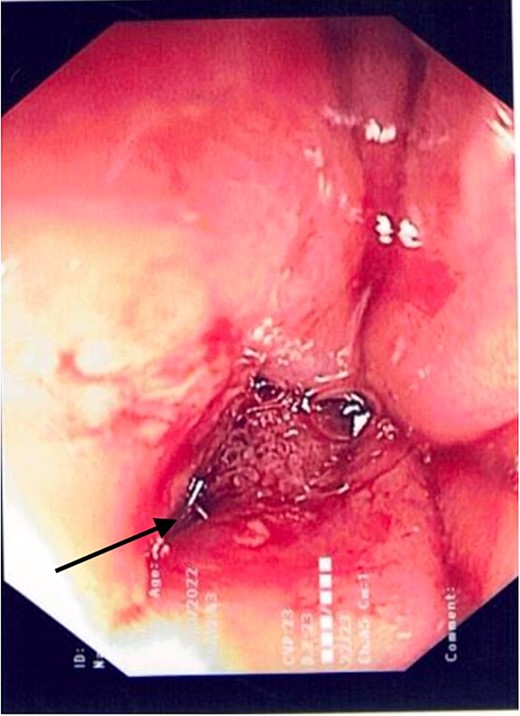

2L of pus was evacuated during laparoscopy, and it was converted to open due to limited views. At this stage, there was no obvious perforation. The entire colon was inspected, following splenic flexure and caecal mobilization. On inspection of the stomach, the wrap was intact with an unremarkable leak test. The decision was made to proceed with gastroscopy, whereby a 3 mm pinhole defect was seen at the GOJ at the 9 o’clock position, as shown in Fig. 2. Three haemostatic Cook Medical Instinct clips were placed, from distal to proximal, ensuring there was stable apposition of the perforated mucosa prior to deploying, as demonstrated in Fig. 3. Following this, the NGT was re-inserted under vision. The midline laparotomy was partially closed and Abthera dressing placed. The patient was taken to ICU intubated, with definitive closure performed 48 h later.

Gastroscopic image demonstrating the successful application of haemostatic clips at the site of perforation (arrow).